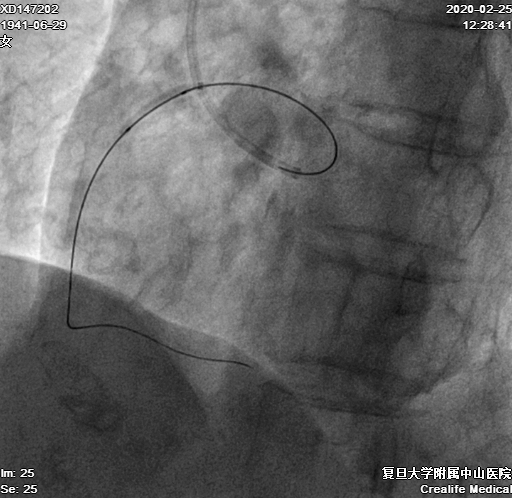

LM未见狭窄、LAD近段狭窄50%,中段30%,D1近中段狭窄80%,、LCX中段狭窄30%、OM未见明显狭窄,RCA近段狭窄50%,中段完全闭塞,远段由自身桥侧枝及心外膜侧枝血管提供显影(图1-3)

图1-3